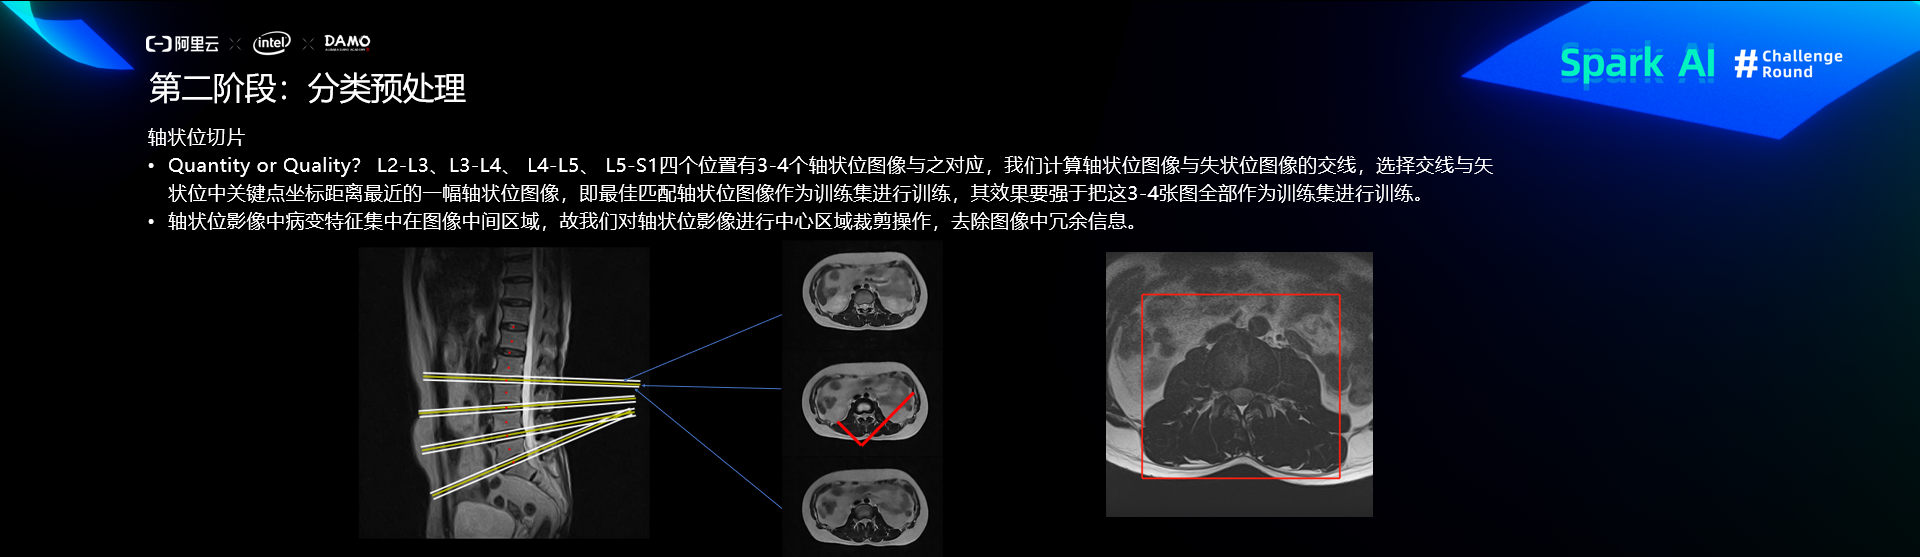

预处理